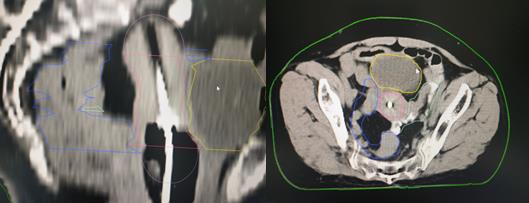

现代腔内近距离放疗技术,即三维后装近距离放疗技术,使用的放射源主要是铱192。通过先进的计算机技术,CT成像技术,自动控制技术等,实现三维后装近距离放疗,是一种个体化的精准近距离放疗技术。一般完成体外放疗剂量45-50Gy后,大部分肿瘤会得到有效杀伤,但由于受到周围肠管及膀胱等正常器官的剂量限制,宫颈肿瘤仍未达到根治剂量,还有残留,若此时停止治疗,肿瘤很快就会复发。为进一步提高宫颈肿瘤放疗剂量,此时采用三维后装近距离腔内照射,将小型化疗的放射源送到宫腔及宫颈肿瘤部位,对残余肿瘤单次给予很高剂量照射,而周围正常组织照射剂量极速下跌,完美的实现高剂量杀灭肿瘤,正常组织受到较低剂量的影响,从而提高肿瘤患者的生存年限及生存质量。